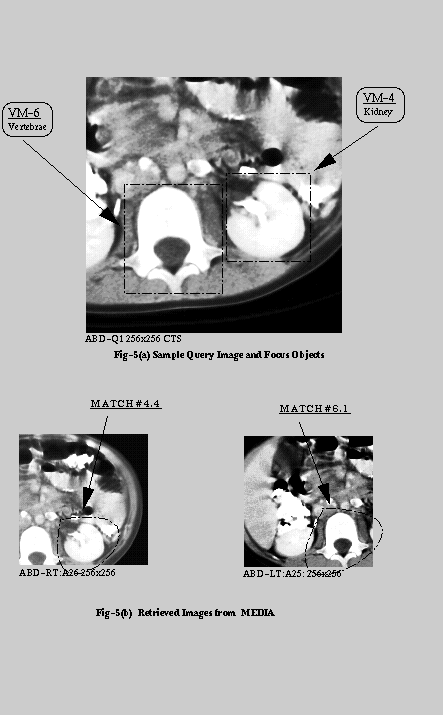

The rectangular windows specify the focus, and the ovals in the bottom images specify the corresponding matching images those were retrieved by the IMED system.